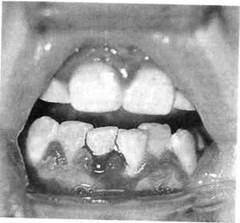

Хронический катаральный гингивит в стадии обострения характеризуется болевыми ощущениями, резкой спонтанной кровоточивостью десен. При этой форме воспаления десневого края часто отмечается поражение всех трех участков десны. Из анамнеза можно установить, что ребенок периодически страдал кровоточивостью десен и ранее (рис. 8.2; 8.3).

Рис. 8.2. Обострение хронического катарального гингивита при лечении несъемной ортодонтической техникой.

Рис. 8.3. Обострение хронического катарального гингивита.